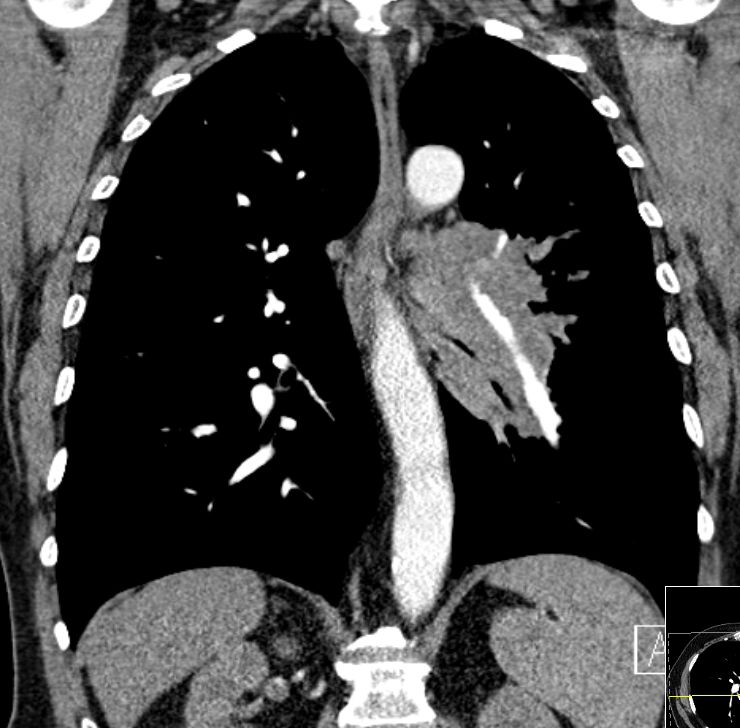

zentrales, kleinzelliges Lungenkarzinom rechter OL mit Infiltration des Mediastinums T4 N3 M1 oss ? 68jährige Patientin im reduzierten AZ und normalen EZ. Unsicherer Gang bei Kreislaufstörungen. Belastungsdyspnoe. Deutliche Leistungsschwäche. Supraklavikulargruben: links frei, rechts auffälliger Tastbefund. ![]() |

![]() |